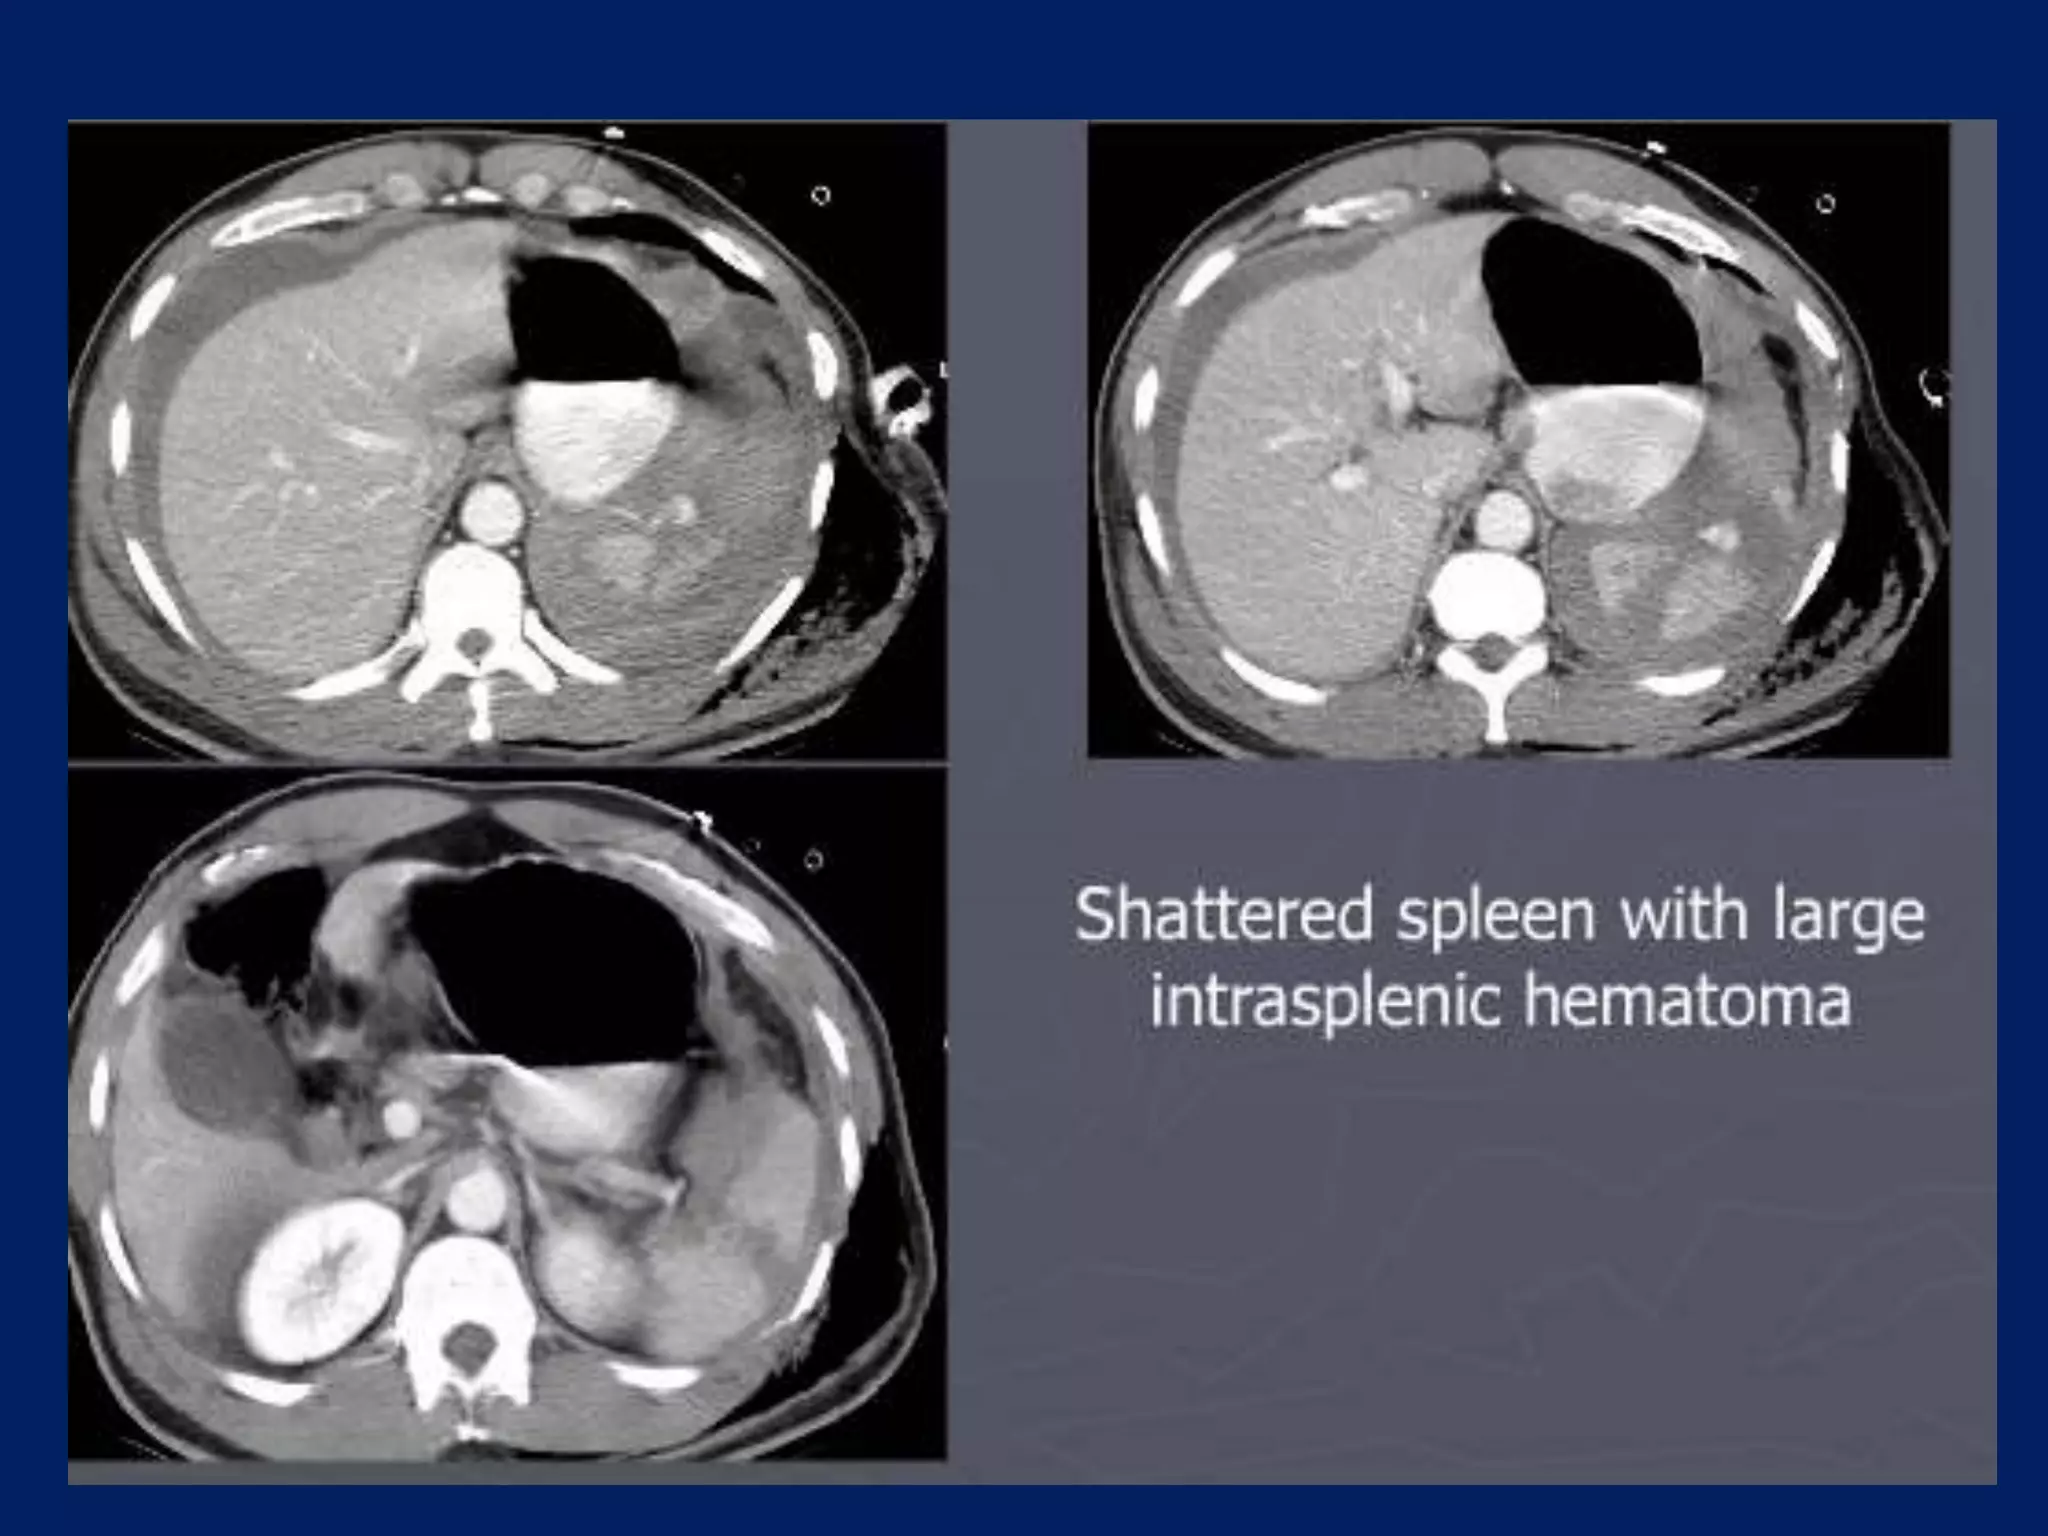

This document discusses imaging of the spleen and summarizes various congenital anomalies and pathologies that can affect the spleen. Some common congenital anomalies mentioned include accessory spleens, asplenia, polysplenia, and splenic fusions. Acquired conditions like repeated infarctions, infiltration, tumors, and cysts can also cause splenomegaly or functional asplenia. Wandering spleen is discussed as a rare congenital anomaly where the spleen lacks attachments and is mobile within the abdomen. Various grades of splenic lacerations and examples of splenic imaging findings are also briefly summarized.